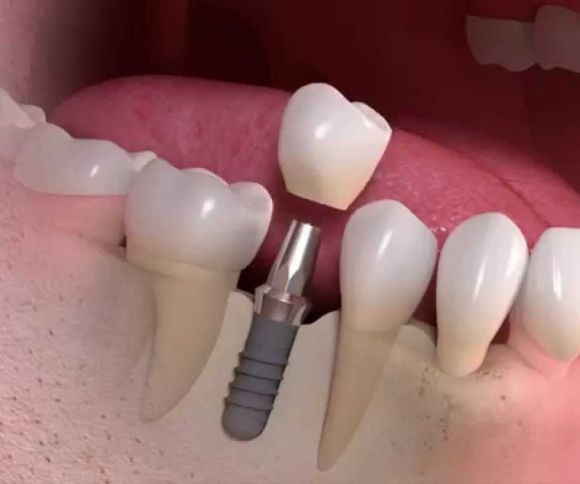

Restorative dental treatments aim to restore damaged or decayed teeth to their natural function and appearance.